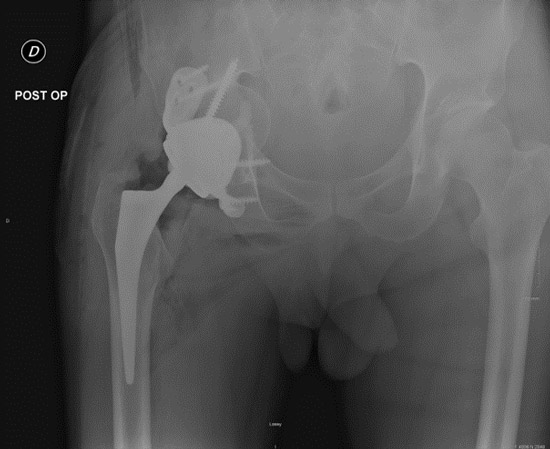

Postoperative imagery